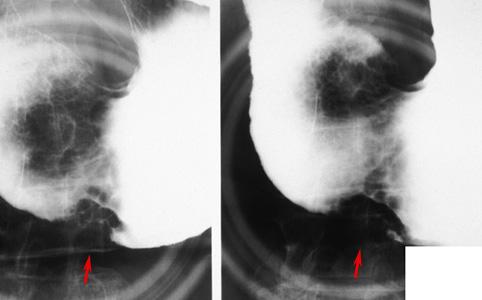

점막하 종양의 형태를 나타낸 호산구성 육아종(위 아니사키스 의심)

기생충질환/아니사키스

위(부위)/전정

X-P

15~19